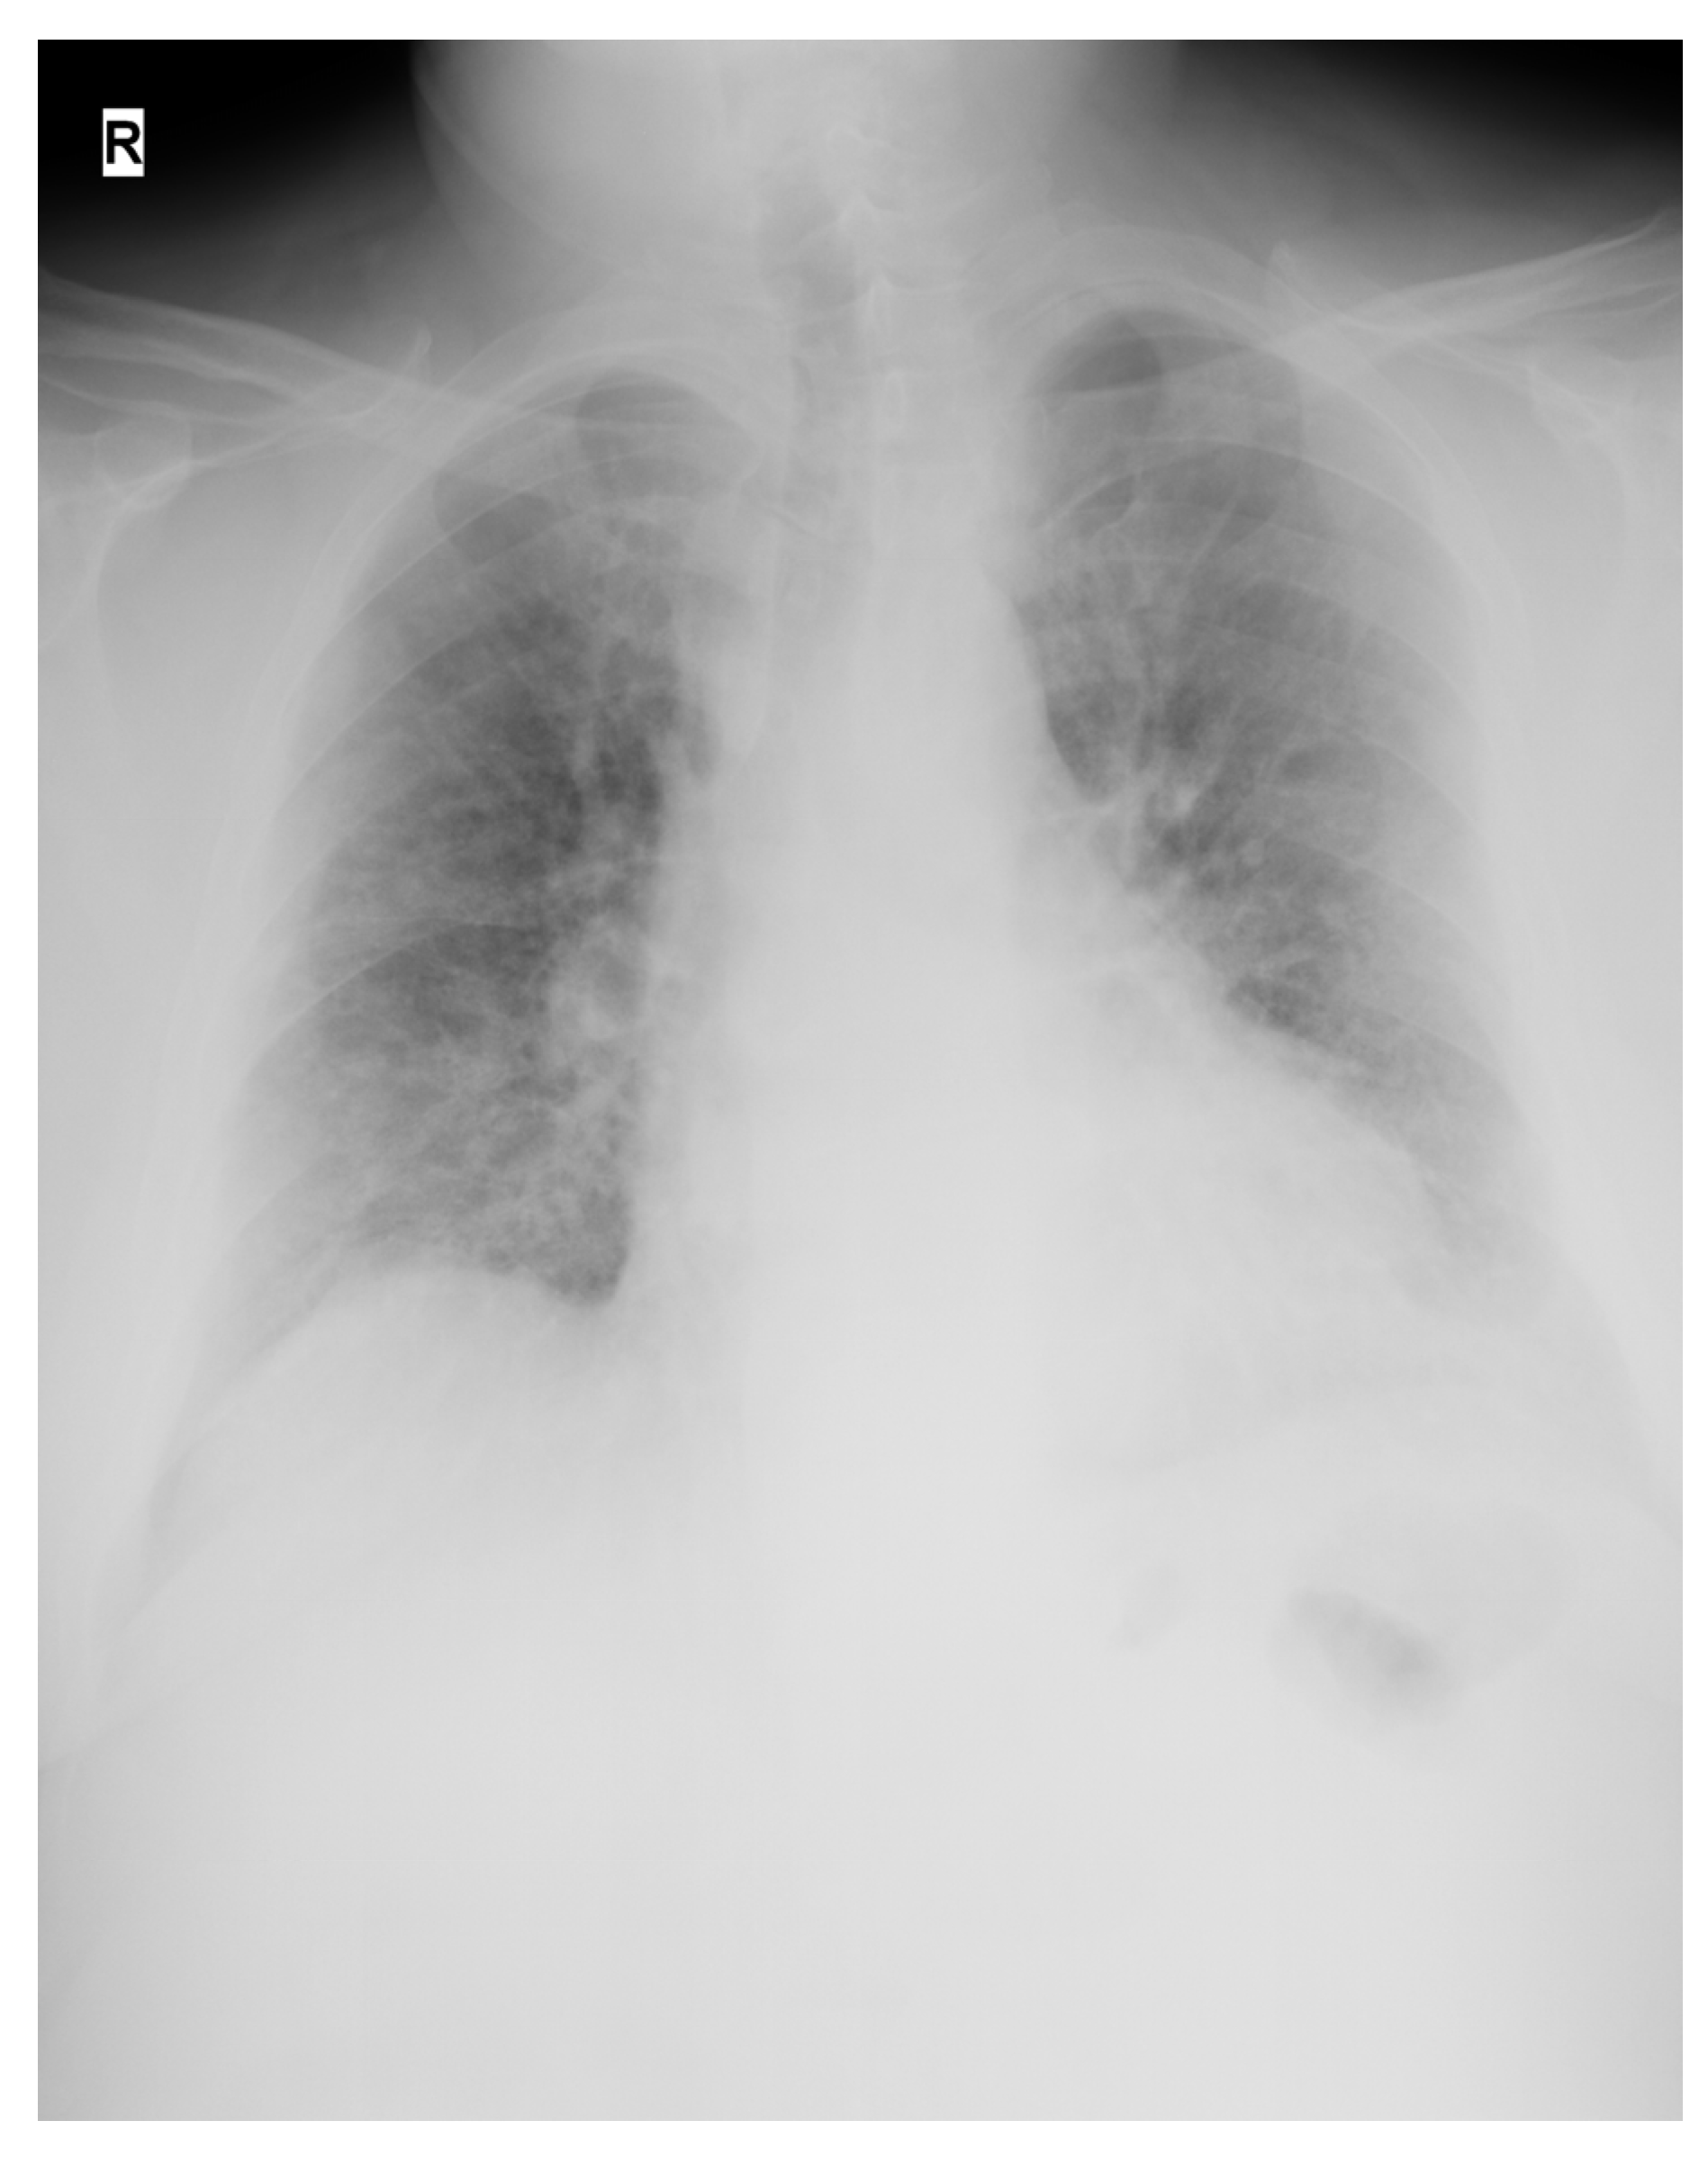

| Presentation | A 52-year-old man presented in the ER with malaise, fever, severe cough, tachypnea, tachycardia, and dyspnea, which started 2 days before the presentation. Upon rapid assessment, the patient had low oxygen saturation and showed signs of respiratory failure. The decision was made to transfer the patient to the ICU after preliminary radiological examination. |

| Day 23 | Lung CT was performed for pulmonary re-evaluation. |